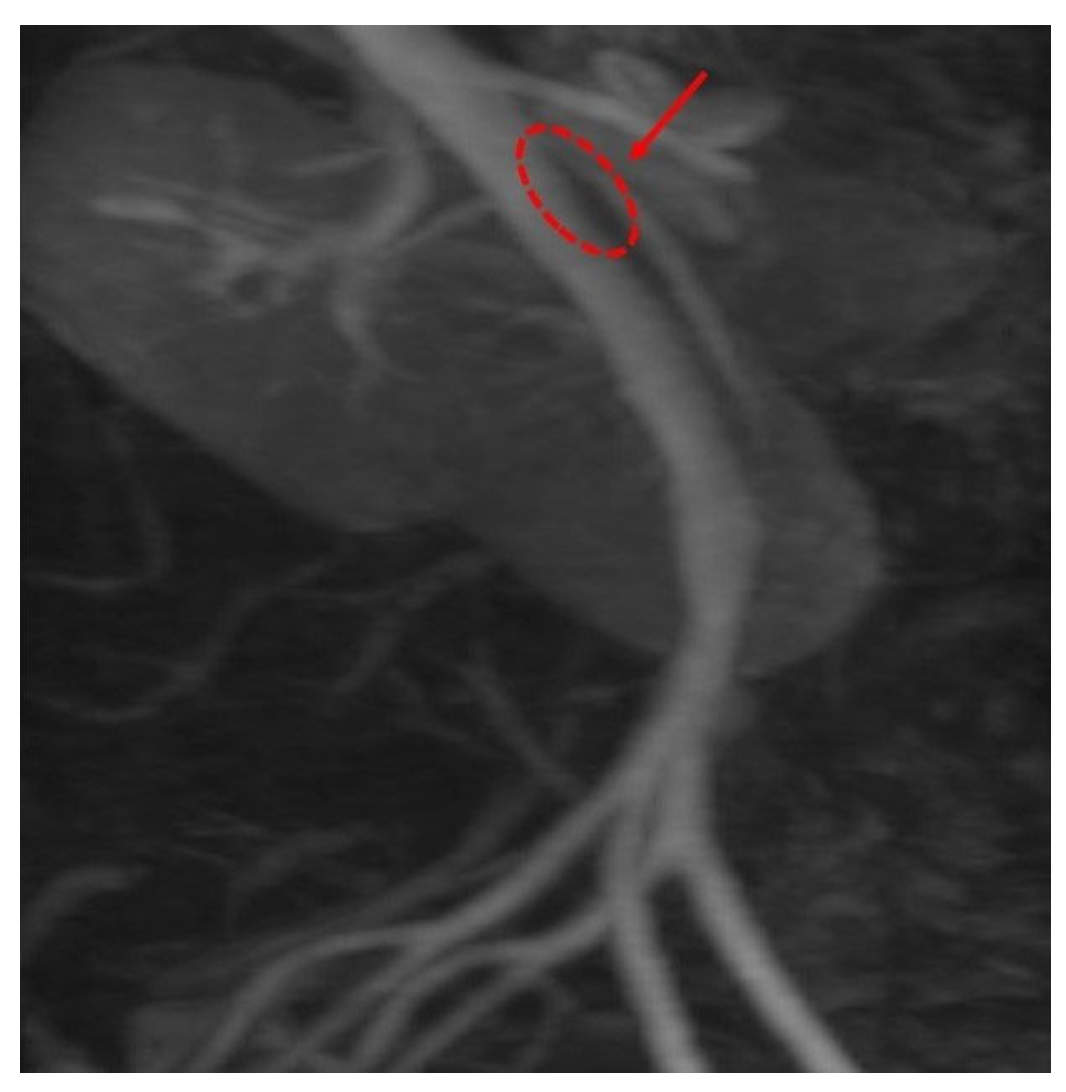

An upper GI contrast study demonstrated an incomplete fixed stenosis due to an apparent extrinsic pressure effect on the second portion of the duodenum, which impeded the passage of contrast medium. No intrinsic strictures or obstructive lesions were identified. Additional findings included antral dyskinesia and antiperistalsis, evidenced by delayed passage of contrast material into the duodenal bulb. A folding of the gastric fundus was also noted Figure 1.

Figure 1. Upper GI contrast study: incomplete fixed stenosis due to an apparent extrinsic pressure effect on the second portion of the duodenum. (A): Delayed progression of contrast material into the duodenum; (B): Gastric cascade configuration.